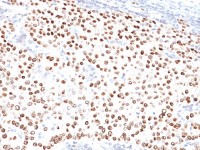

IHC-P analysis of human leiomyoma tissue using GTX20959 Desmin antibody [D33] (ready-to-use).